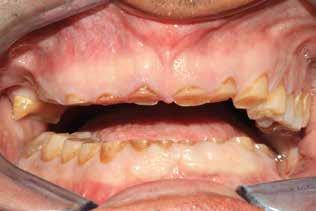

CASO CLINICO N.6

Riabilitazione implantoprotesica in paziente con rischio assoluto alto

Il paziente del seguente caso, già visitato nel 2019, è poi tornato nel 2021 per una rivalutazione. Già durante la prima visita era stata rilevata una situazione di compromissione generale, sia dal punto di vista igienico, sia funzionale.

Alla visita di rivalutazione è emerso un ulteriore peggioramento della situazione, confermata anche dall’esame radiografico, con parodontopatia, sanguinamento al sondaggio, infiammazione diffusa, alitosi, difetto parodontale verticale mesiale a 2.3, residui radicolari 1.4, 1.6, 1.7, 3.6, 3.8 e carie destruenti di 1.5, 2.6, 3.5, 3.7 (con lesione endoperio) e 4.7 con estrusione e carie (Figg. 1, 2)

Il paziente, un uomo di 67 anni, ha confermato l’anamnesi precedente, ossia di essere portatore di

molteplici patologie: sindrome metabolica in discreto compenso farmacologico (riferita assunzione di metformina 500 mg, enalapril, acido acetilsalicilico, atorvastatina) e in terapia sostitutiva con levotiroxina perché operato di tiroidectomia totale per un tumore in giovane età; deambulazione autonoma con aiuto del bastone per via di un intervento al ginocchio abbastanza recente (riferito 6 mesi prima intervento di protesi totale di ginocchio).

Spesso è importante ascoltare i pazienti mentre descrivono la loro vita di tutti i giorni, perché si possono scoprire dati importanti che il paziente sottostima. In questo caso, è stato fondamentale chiedere al paziente se avesse problemi a dormire o assumesse terapie specifiche per agevolare il sonno, per venire a conoscenza che da tempo soffre di apnee notturne per le quali indossa la CPAP. È stato spiegato al paziente che una riabilitazione protesica corretta avrebbe migliorato anche la situazione delle apnee.

Si è consigliato di procedere per gradi, con bonifica di tutti gli elementi malati e irrecuperabili e successivamente sostituire gli elementi mancanti o con protesi rimovibili o con una protesi fissa sostenuta da impianti (Fig. 3).

La proposta che il paziente ha accettato è stata poi quella, previa bonifica di tutti gli elementi irrecuperabili, di riabilitare con impianti prima il 1° e 4° quadrante e in seguito il 2° e 3° e procedere poi alla protesi definitiva in un’unica soluzione.

Prima di procedere con gli interventi si è richiesto degli ematochimici di routine, per controllare soprattutto la glicemia, l’emoglobina glicata, la coagulazione, la vitamina D e i sali minerali.

Al controllo ematologico è emersa una emoglobina glicosilata molto superiore la percentuale accettabile a procedere (il valore era 9,3%) e deficit di D-25OH che è stato risolto con una terapia di ripristino con colecalciferolo 25000 U.I. Data la stretta correlazione tra emoglobina glicata e affezioni orali, è ormai routine seguire un percorso che porta alla bonifica della bocca e contestualmente, che aiuta il paziente anche con il controllo della glicemia. In prima battuta comunque, abbiamo sottoposto il paziente a una seduta orale. Per via del suo stato di salute (abbiamo stabilito per lui un rischio alto) durante ogni seduta invasiva abbiamo sempre monitorato il paziente con rilevazioni multiple dei parametri e reperendo un accesso venoso pe-

riferico. Si è eseguito la maggior parte delle estrazioni in un’unica seduta operatoria, a esclusione degli elementi 2.6 e 4.7 che sono stati mantenuti perché presentavano mobilità ma non segni di focolai infettivi attivi e che si è deciso di estrarre in un secondo momento. Il follow-up post estrattivo ha consentito anche di valutare la risposta tissutale e la guarigione degli alveoli. Non è stata sospesa la terapia con l’acido acetilsalicilico. Il PRGF è stato importante per evitare alveoliti che avrebbero rallentato la guarigione (Figg. 4-6).

Dopo tre mesi dalla prima fase estrattiva sono stati ripetuti gli esami ematochimici dai quali l’emoglobina glicata del paziente è scesa a 7.2%. Abbiamo pertanto avviato con lo studio pre-implantare che prevede la ceratura diagnostica e gli esami radiologici più avanzati per scegliere i giusti impianti e la loro sede corretta.

L’esame CBCT ha rivelato un quantitativo di osseo sufficiente a procedere con l’intervento implantare, anche se erano ancora visibili le zone delle estrazioni; inoltre ha evidenziato una lesione osteolitica a carico del 3.5 che abbiamo dunque deciso di estrarre (Figg. 7-20).